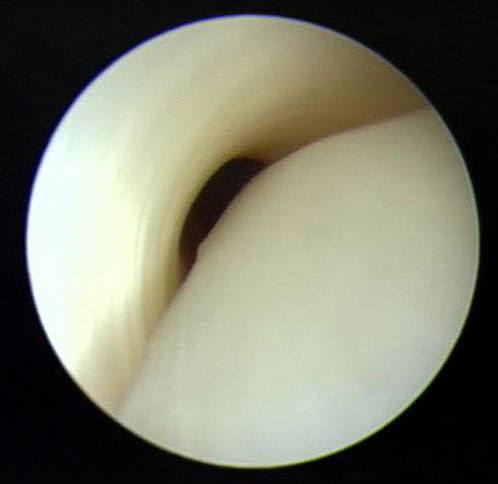

3. Alternativ ist eine Transposition der Sehne des M. flexor digitorum longus auf das Os naviculare möglich (FDL-Transfer). Das tendoskopische Debridement bietet sich insbesondere an bei Patienten mit im MRT noch weitgehend intakter Sehne (Abb. 21)."> 3. Alternativ ist eine Transposition der Sehne des M. flexor digitorum longus auf das Os naviculare möglich (FDL-Transfer). Das tendoskopische Debridement bietet sich insbesondere an bei Patienten mit im MRT noch weitgehend intakter Sehne (Abb. 21)." srcset="/assets/images/x/20-4wazvyk6qcpt2xs.jpg 1x, /assets/images/y/20-a6v6m55vtx2zmry.jpg 1.5x, /assets/images/q/20-ye4s9jha1jrvcge.jpg 2x" width="270" height="240" loading="lazy">

Abbildung 20

3. Alternativ ist eine Transposition der Sehne des M. flexor digitorum longus auf das Os naviculare möglich (FDL-Transfer). Das tendoskopische Debridement bietet sich insbesondere an bei Patienten mit im MRT noch weitgehend intakter Sehne (Abb. 21)."> 3. Alternativ ist eine Transposition der Sehne des M. flexor digitorum longus auf das Os naviculare möglich (FDL-Transfer). Das tendoskopische Debridement bietet sich insbesondere an bei Patienten mit im MRT noch weitgehend intakter Sehne (Abb. 21)." srcset="/assets/images/0/21-n45853s2pe0a6dv.jpg 1x, /assets/images/w/21-rjh7v27n1j3bg4x.jpg 1.5x, /assets/images/w/21-7spvf34wgeytm3k.jpg 1.844x" width="270" height="240" loading="lazy">

Abbildung 21